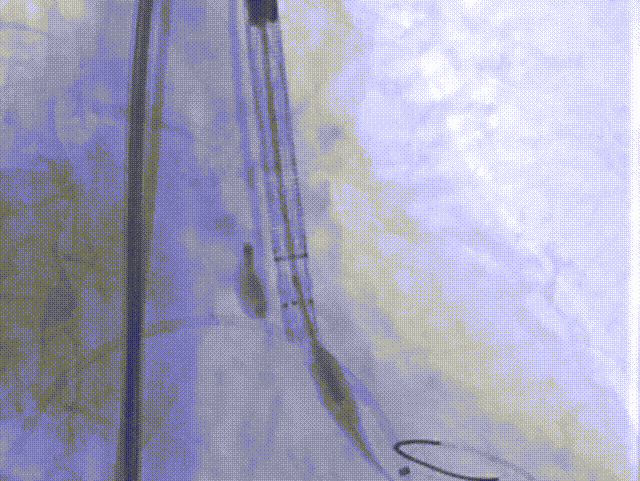

瓣膜形态

18球囊后扩张

瓣膜最终形态